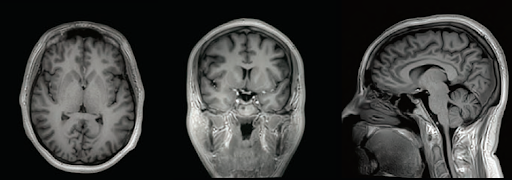

Vantage Galan 3T MR от Canon Medical Systems создана для получения высококачественных изображений и оптимизации рабочего процесса врача-диагноста. Комплекс различных технологий позволил создать тихую, быструю и экономичную МР систему.

Мультифазная технология РЧ-системы обеспечивает высокую однородность магнитного поля во всех областях сканирования.

Технология MUTE 3D T1 позволяет уменьшить шум на полученных изображениях.

Приложения mUTE2 подавляют высокоскоростное переключение градиентного поля, позволяя обеспечить еще более чистые и качественные изображения за счет снижения акустического шума.